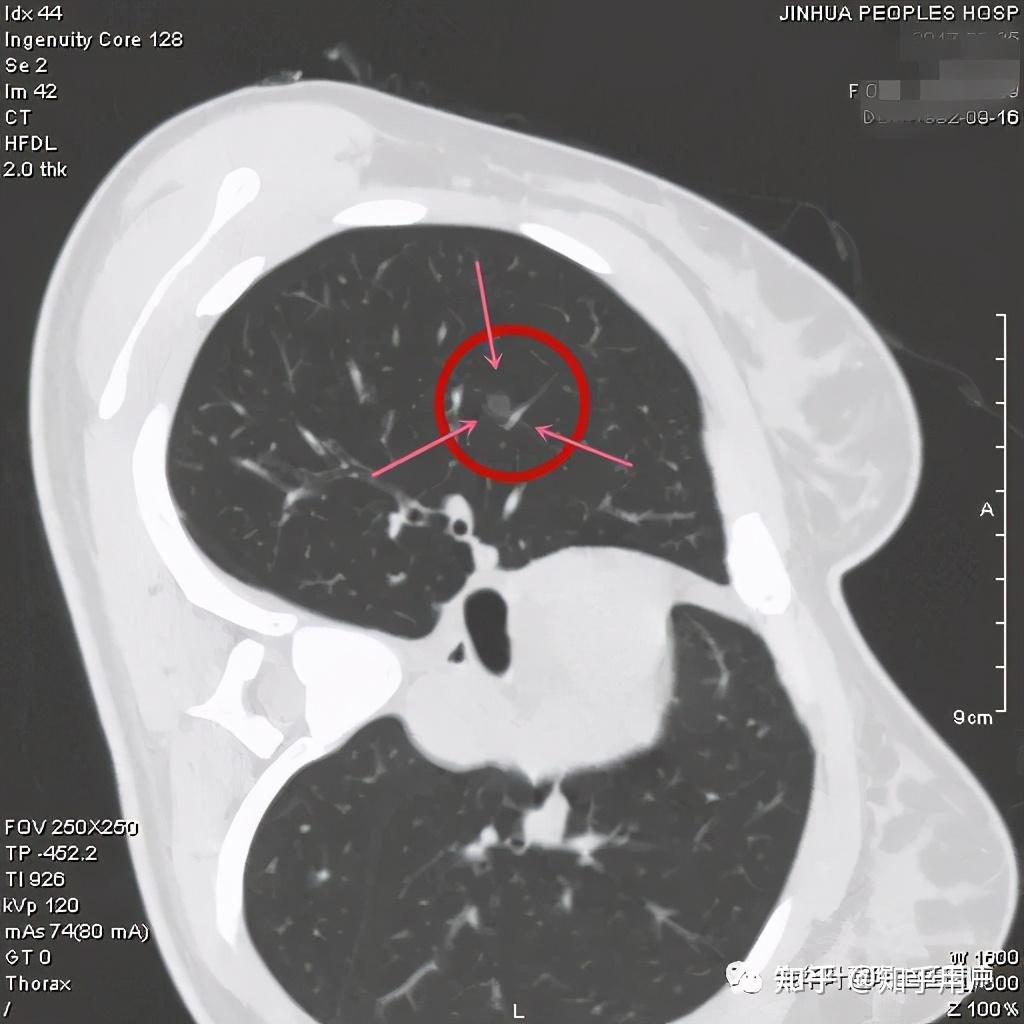

影像上的表现,原位腺癌应该是5-30毫米的纯磨玻璃结节,密度均匀,CT值在-600以下,极少有空泡、毛刺、胸膜牵拉和分叶,可以有血管穿行,但无血管弯曲。当然若病灶在10毫米以上时,诊断原位腺癌要慎重,因为1厘米以上的病理上是原位腺癌的少见。

看着,非常不错,以后原位腺癌与非典型增生不是癌了,不需要手术了,至少不能按恶性肿瘤的方式进行手术了。这是好事!但真的到了临床上,如何把握,我看仍是前路漫漫,迷雾重重!我们先举几个例子,来看看影像上如何来区分AAH、AIS、MIA以及浸润性腺癌。下面的四幅CT图分别各是其中的一种,是我们术后有病理依据确诊的病例,你能分出哪张是哪种吗?

有没有高手能分辨出来?我是一头雾水,根本分不清到底哪个是哪种。都是纯磨玻璃结节,都是瘤肺边界清楚,大小都在1厘米左右或以下。现比如下面这四幅CT图也是分别为AAH、AIS、MIA以及浸润性腺癌(贴壁型),你能分得清楚哪幅图是哪种吗?

这几乎就是四胞胎,长的没什么区别,但病理类型天差地别。现在把AAH与AIS剔除出恶性肿瘤后,更是差别巨大了,是癌与非癌的区别了,但没有手术切除病检的情况下,你如何来区分?